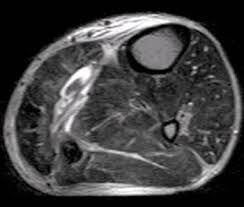

A quadriceps tendon tear or strain is an injury to the quadriceps tendon (the tendon that works with the muscles in the front of the leg to straighten the leg). Tendons are prone to injuries caused by overuse. It usually requires surgery and physical therapy to regain full knee function. Most often found in people over the age of 40, a tear of the gluteus tendons may happen from a fall or repetitive injury to the tendon. This allows the muscles to continue to pull the on the bone and perform their function. A tendon rupture is a partial or complete tear of your tendon. However the long tendons of the limbs are vulnerable to damage during exercise or as a result of trauma. Tendons are tough bands of tissue that attach your muscles to your bones.

The quadriceps tendon works with the muscles in the front of your thigh to straighten your leg. But in older people and in those with certain diseases (such as gout and hyperparathyroidism), tendon rupture may occur. Tendons are tough bands of tissue that attach your muscles to your bones. There are two peroneal tendons in each leg. A quadriceps tendon tear is an injury that occurs when the tendon in the front of your thigh tears partially or entirely. A tendon injury may seem to happen suddenly, but usually it is the result of many tiny tears to the tendon that have happened over time. A tear or injury due to rheumatoid arthritis if a person visits the doctor with a tendon injury, a doctor will carry out an initial physical examination of the injured area. This injury is most commonly due to an abrupt, forcefully impact on your thigh.